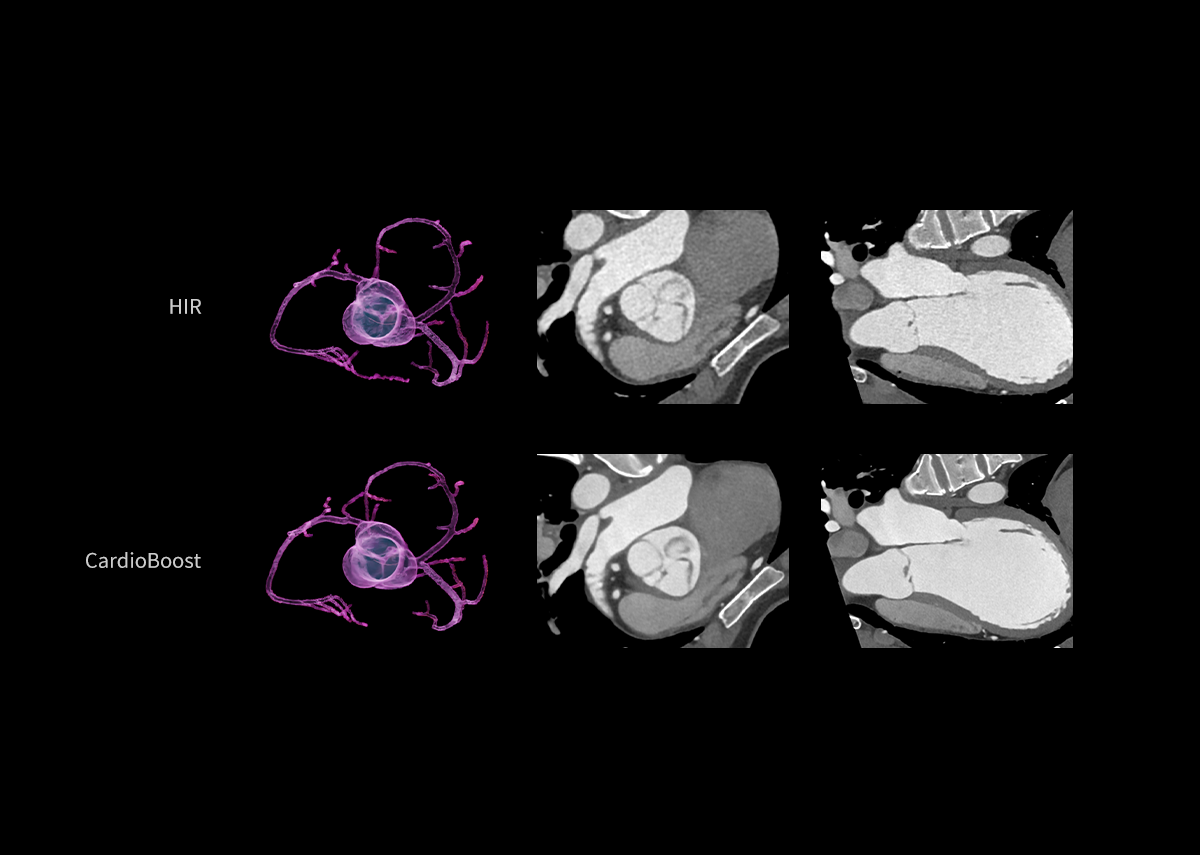

Throughout the iterative loop of forward and backward projection between the raw data domain and the image domain, AIIR consistently takes into account the accurate modeling of optics, noise, anatomy, and physics statistics. Additionally, AIIR integrates deep learning-based de-noising technology, supplanting the conventional regularization role of MBIR in the optimization reconstruction process.

In brief, AIIR utilizes deep learning-based AI technology to attain robust noise reduction and natural image texture, while incorporating MBIR technology to achieve precise anatomical structure representation and artifact suppression. This technique surpasses the limitations of using either MBIR or deep learning reconstruction (DLR) independently.